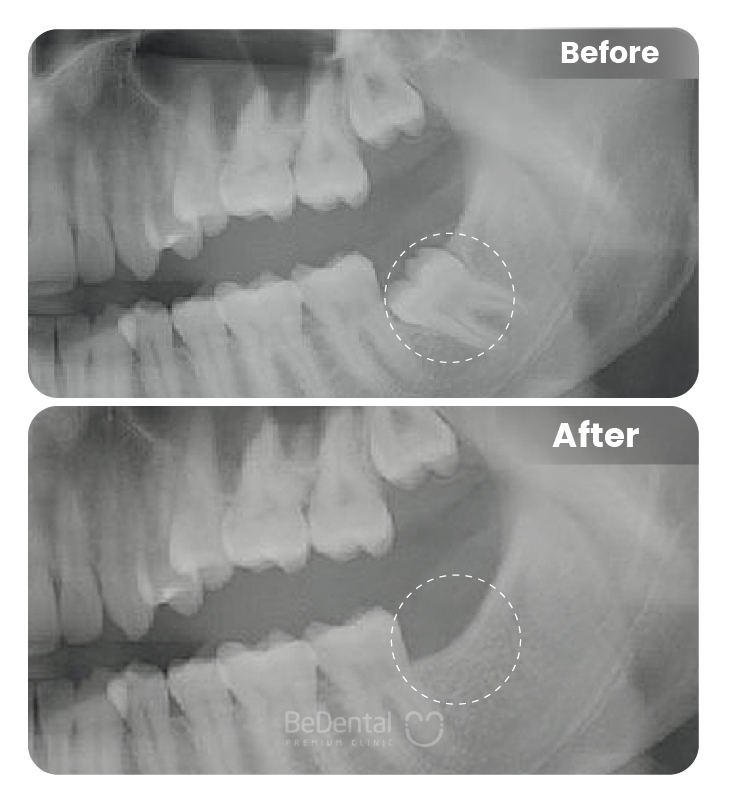

Nhổ răng khôn là thủ thuật nha khoa nhằm loại bỏ răng số 8 mọc lệch, mọc ngầm hoặc gây đau nhức, viêm nhiễm. Với sự hỗ trợ của công nghệ hiện đại và gây tê an toàn, quá trình nhổ răng diễn ra nhanh chóng, hạn chế đau, giúp ngăn ngừa biến chứng và bảo vệ sức khỏe răng miệng lâu dài.